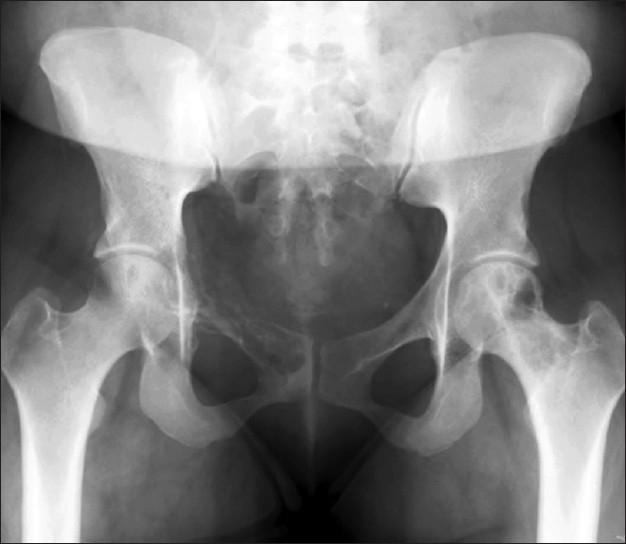

Sinus histiocytosis with massive lymphadenopathy (SHML) or Rosai-Dorfman disease (RDD) is an uncommon but well-defined benign self-limited clinicopathological entity. It mainly involves lymph nodes. Extranodal involvement is seen in up to 43% of cases, with the most common location in the head and neck region. Primary RDD occurring in the bone is rare with only twelve cases reported in the literature to date, all diagnosed on histology except one by fine needle aspiration (FNA) cytology. We report a case of RDD diagnosed by FNA cytology in a 28 year-old female presented as an osteolytic lesion of superior pubic ramus where the differential diagnosis included a sarcoma and lymphoma. Based on the cytologic findings, a diagnosis of a RDD was considered during the rapid FNA on site with no clinical history provided. The diagnosis of RDD was further confirmed by immunohistochemical stains and histology diagnosis. Our findings show that even in the absence of a clinical history, FNA is a less invasive and a very reliable tool for the diagnosis of SHML (RDD).

伴有巨大淋巴结病的窦组织细胞增生症(SHML)或罗萨伊-多夫曼病(RDD)是一种罕见但明确的良性自限性临床病理实体。它主要累及淋巴结。结外受累见于高达43%的病例,最常见于头颈部区域。原发性RDD发生于骨骼者罕见,迄今为止文献中仅报道了12例,除1例通过细针穿刺(FNA)细胞学诊断外,其余均经组织学诊断。我们报告1例28岁女性患者,通过FNA细胞学诊断为RDD,表现为耻骨上支溶骨性病变,鉴别诊断包括肉瘤和淋巴瘤。基于细胞学发现,在现场快速FNA时考虑诊断为RDD,当时未提供临床病史。RDD诊断通过免疫组化染色和组织学诊断进一步得到证实。我们的研究结果表明,即使没有临床病史,FNA也是诊断SHML(RDD)的一种侵入性较小且非常可靠的工具。